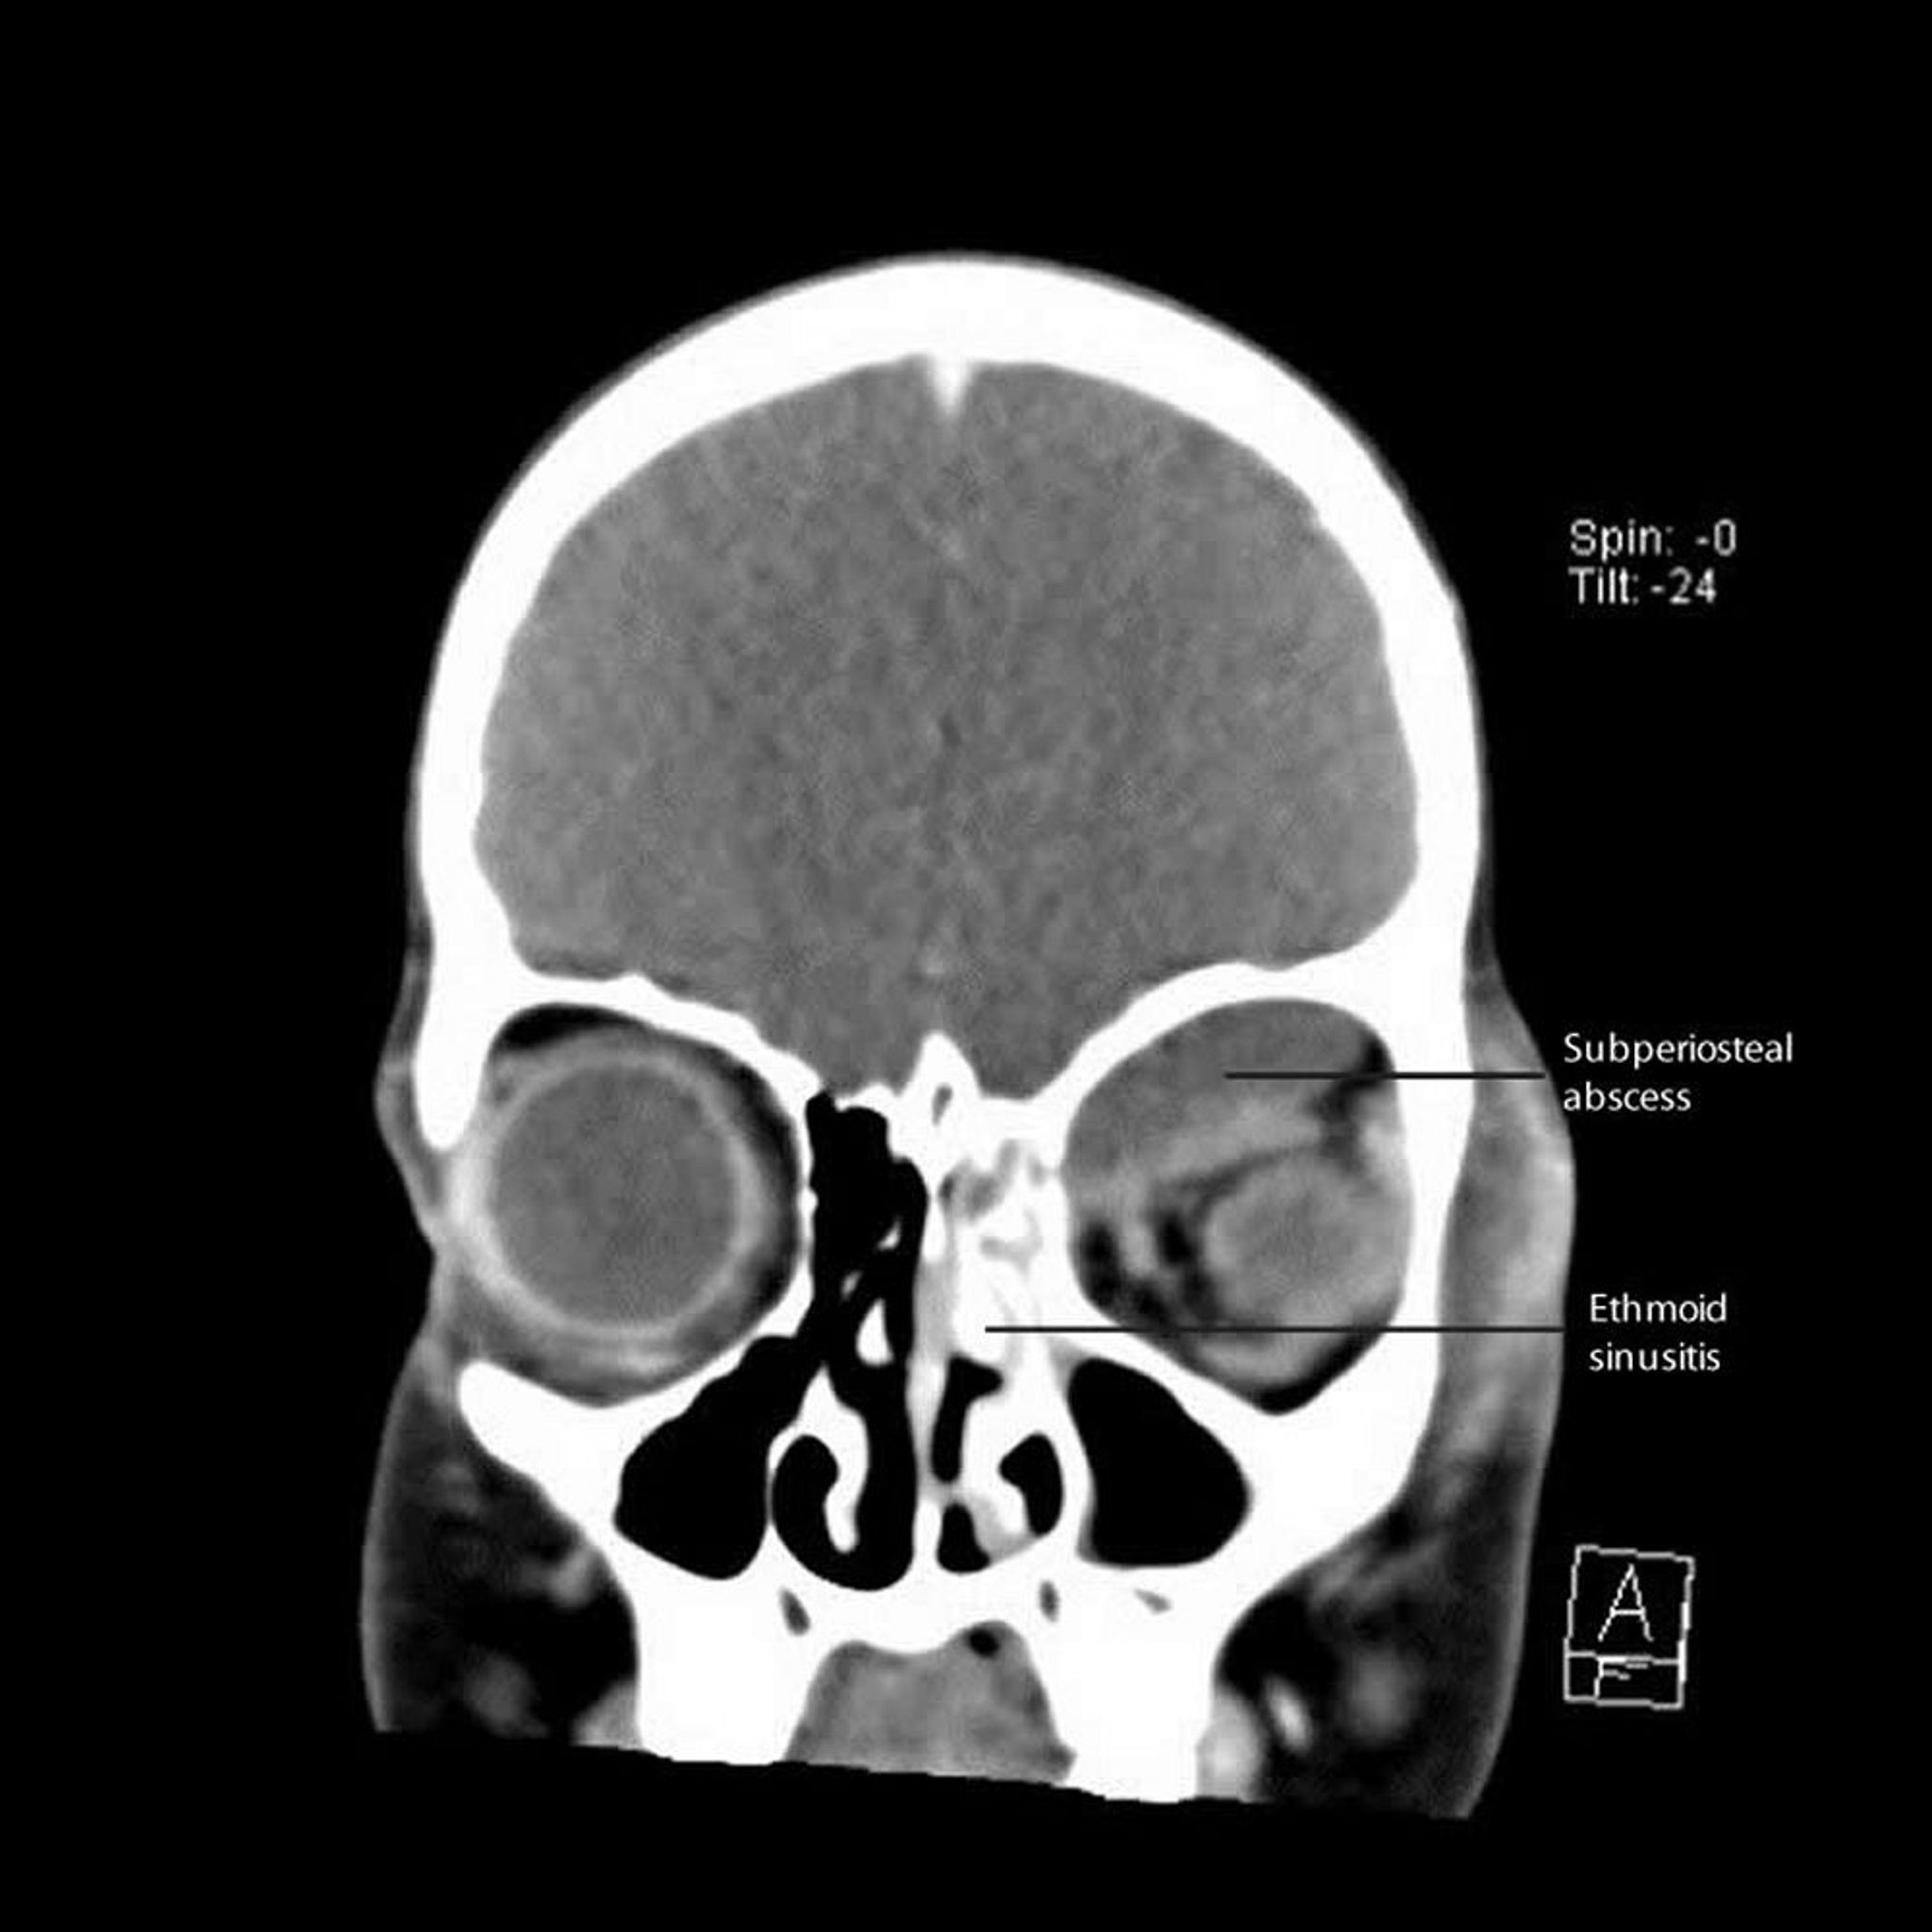

Sinusitis etmoidal con absceso subperióstico

Esta TC muestra una sinusitis etmoidal izquierda con absceso subperióstico adyacente a lo largo de la pared medial y el techo de la órbita.

CT courtesy of James Garrity, MD.